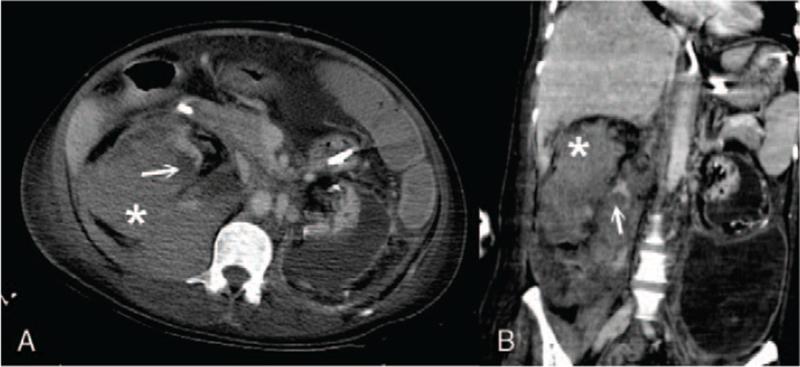

The patient's laboratory results indicated an abrupt drop in hemoglobin level. Emergent abdominal computed tomography (CT) showed a rupture of the lower pore of the left kidney, with massive hemoretroperitoneum. A second sudden reduction in hemoglobin level occurred 2 months later during the same admission course, with poor response to urgent blood transfusion. Contrast extravasation at the lower pole of the right kidney and posterior pararenal space along with a subcapsular hematoma was revealed on abdominal CT.

After the first episode, immediate postprocedural angiography showed total occlusion of the left renal artery without contrast extravasation. Follow-up CT performed 10 days after the first TAE showed a residual left perirenal hematoma that extended to the left retroperitoneal and left upper pelvic region, without active bleeding. No follow-up imaging was done after the second TAE except for immediate postprocedural angiography, which showed no additional contrast extravasation of the right renal artery.